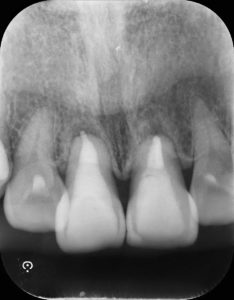

術後

変色部分の改善を確認した後、充填処置を行った。

今回は変色部分の改善と歯質をできるだけ温存する方法を取り、審美的改善ができました。